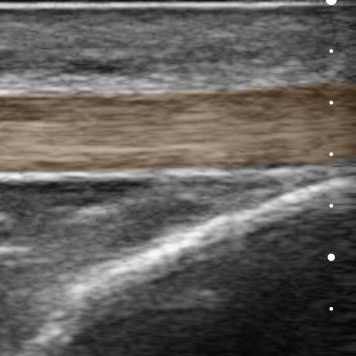

The new Clarius MSK AI features advanced artificial intelligence technology designed to identify, measure, and label key anatomical structures in real-time, providing accurate and reliable ultrasound information to clinicians. This not only speeds up workflows, but also boosts confidence in diagnosis and treatment plans. By outputting probabilities for each pixel within the image, the AI determines the particular tendon visible, allowing for quick and accurate assessments. Additionally, the AI makes it a valuable tool for training, allowing less experienced clinicians to learn and improve their diagnostic abilities with ease.

MSK AI identifies, measures, and labels key anatomic structures, starting with the patellar tendon, Achilles tendon, and plantar fascia using AI technology. Exclusively for Clarius members, the feature is designed to assist with musculoskeletal (MSK) scanning for specific anatomical sites, including the foot, ankle, and knee. With the colored overlay and automatically-placed calipers, it’s easier for novice users to learn ultrasound anatomy, and more efficient for experienced clinicians to conduct comparative and serial studies where consistent measurements of tendons are critical.

Automatically highlights the tendon, with adjustable opacity

Automatically measures the thickest width of the tendon

Labels the Patellar tendon, Achilles, and plantar fascia